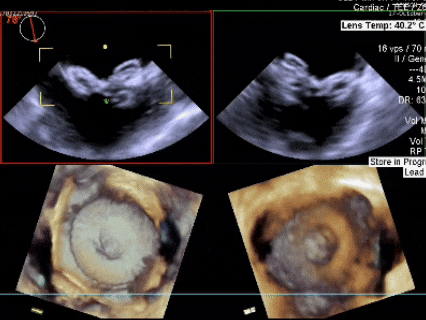

三维下可见房间隔缺损

左盘展开

左盘展开后牵拉成型线使盘面成型,后撤鞘管和钢缆,使封堵器左盘贴靠房间隔

右盘展开

随后固定钢缆不动,回退鞘管,右盘展开

成型锁定

鞘管抵住封堵器后,前顶钢缆,

固定钢缆和鞘管,牵拉成型线锁定